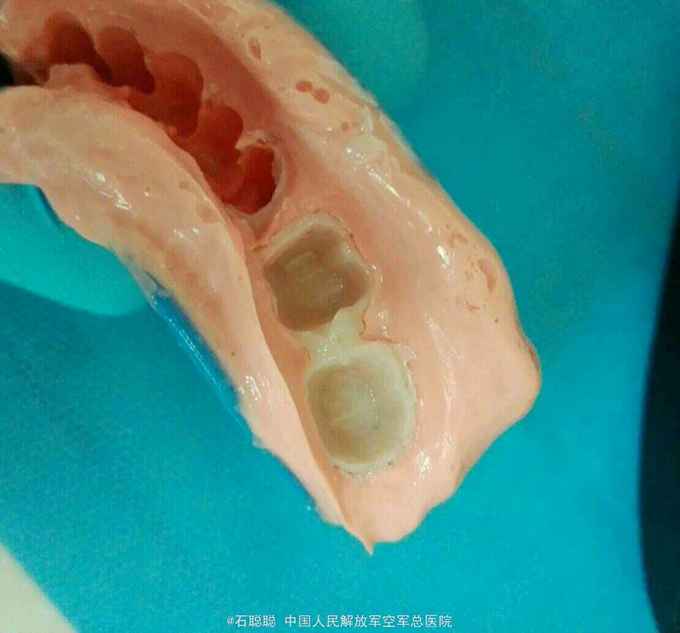

诊断:36、37牙体缺损 治疗计划:36远中、37近中植入纤维桩 烤瓷联冠修复 处置:36、37去除氧化锌暂封,见36远中偏舌侧壁缺损、断面位于龈上1mm,37近中偏舌侧壁缺损、断面平齐龈缘,其余轴壁厚度高度完整 36远中舌侧根管预备桩道,度13mm,1#P钻,37近中舌侧预备桩道,长度14mm,1号P钻,各植入黄玻璃纤维桩一枚,堆树脂核,备牙,取模,比色:A3.5,寄送加工厂,制作临时冠,调合,粘接 一周后复诊: 检查:36、37临时冠完整在位,叩痛-,牙龈未见异常 处置:36、37去除临时冠,清楚粘结剂,试戴36、37银钯合金烤瓷联冠,调合,磨光,粘接